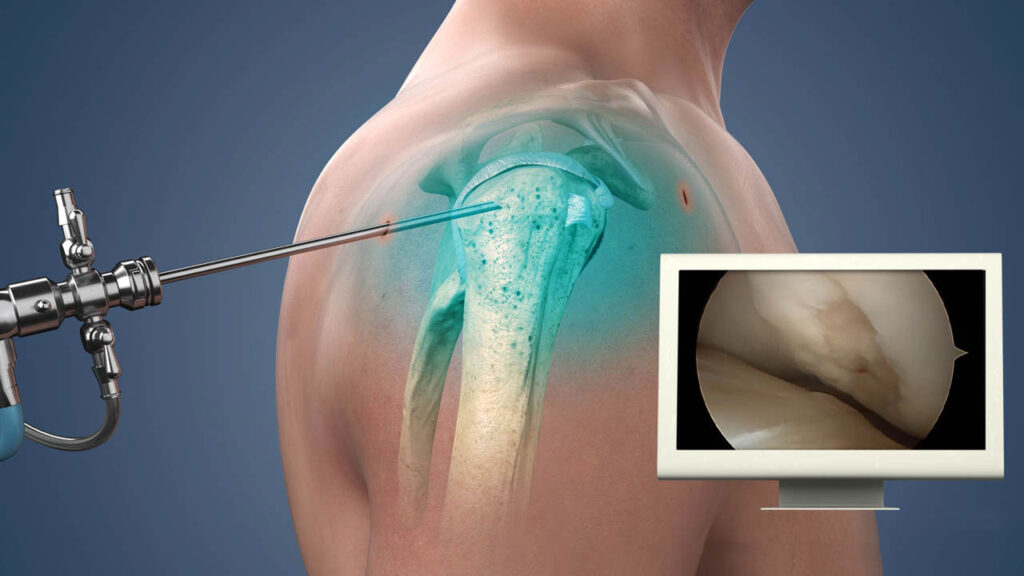

2. Shoulder Arthroscopy:

- Indication: For a variety of shoulder conditions, including rotator cuff tears, shoulder instability, impingement, and labral tears.

- Procedure: Arthroscopy is a minimally invasive technique where small incisions are made, and a tiny camera (arthroscope) is inserted into the shoulder joint. The surgeon can visualize and treat the issue using small surgical instruments.

- Recovery: Recovery time is typically quicker than open surgery, with patients often returning to normal activities within 2-3 months. Full recovery for athletes may take 6-12 months, depending on the complexity of the procedure.